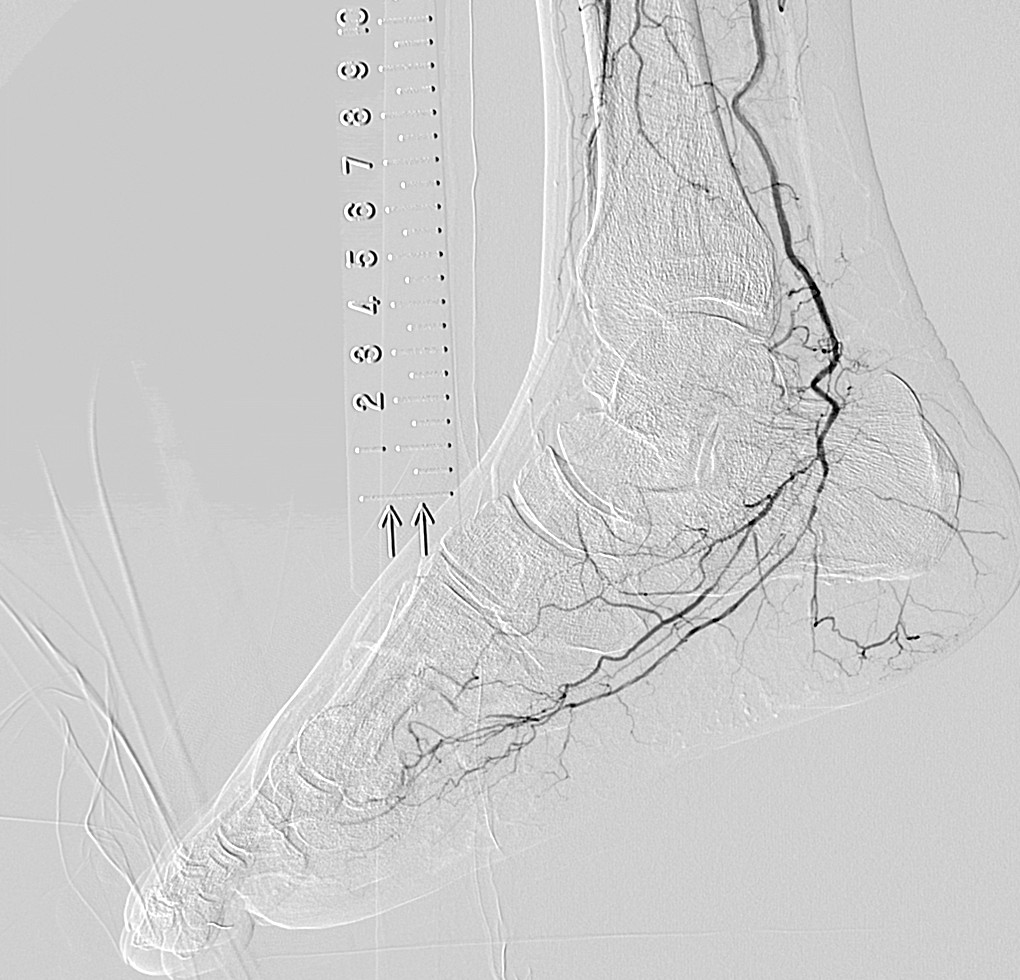

- 首先,双腿能拍到同一画面中这一点很好。还有手术中,由于能够区别使用纵向16英寸、横向16英寸,例如,希望拍摄双腿全长时可以横着跟踪拍摄。采用DSA时,由于迄今为止也都不得不分几次进行拍摄,因此需要患者承担造影剂的负担,而我认为拍摄次数减少对于患者来说是大有裨益的。但即便如此,如果不能拍摄冠状动脉就没有意义了,然而这台机器对于冠状动脉也可以正常拍摄。在搭桥等过程中,无需跟踪也可以将希望看到的区域全部拍摄出来,因此画面不会发生抖动,容易拍摄。

另外,正如曾我医生所说的那样,在跟踪拍摄时,通过将16英寸一侧置于横向,可以一次拍摄到双下肢的全部长度,导管床也在纵向的移动行程长,仅通过移动导管床就可以拍摄到足尖的位置。

- SCORE Chase真的很不错。即使导管床横向移动也能将血管图像自动连接起来,真是非常厉害。为什么之前没有呢?所有来云顶国际医院参观的人都觉得很震惊。

- 曾我

- 大家都说“这个真好啊”。一直以来都是通过手动的方式将血管的图像连接起来的,由于图像间有亮度差,因此非常费功夫。多亏有了SCORE Chase,不需要再这样做了。它会对图像进行校正,瞬间将图像自动连接起来,真的非常方便。

- 即使对于患者细微的动作、震动,都会自动进行抖动补偿处理,因此血管的边缘等变得更加清晰。

- 一之濑

- 是的。的确非常好。图像会随时自动抖动补偿,显示出没有失准的清晰的DSA,所以我都认为成是理所当然的事情了。丝毫没有不适感,感觉适合用于末梢血管的拍摄。